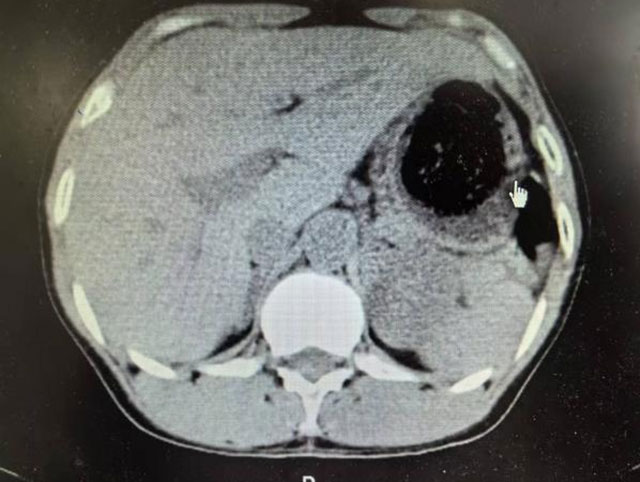

入院后,医生进一步为许女士完善了全腹部CT检查,检查结果提示:小弯侧胃壁广泛肿胀、胃周脂肪间隙稍模糊、胃内两枚胃石;胃镜检查,检查结果提示:慢性萎缩性胃炎、胃多发结石、胃角溃疡。

经科室副主任郭伍斌副教授组织讨论后,决定实施手术取石。完善术前检查后,郭伍斌副教授、罗伟主治医师等在全麻下顺利为许女士实施了剖腹探查+胃切开取石术。术中探查发现胃壁明显水肿,厚约1cm;胃腔内潴留胃结石两枚,最大约7*6*6cm³。